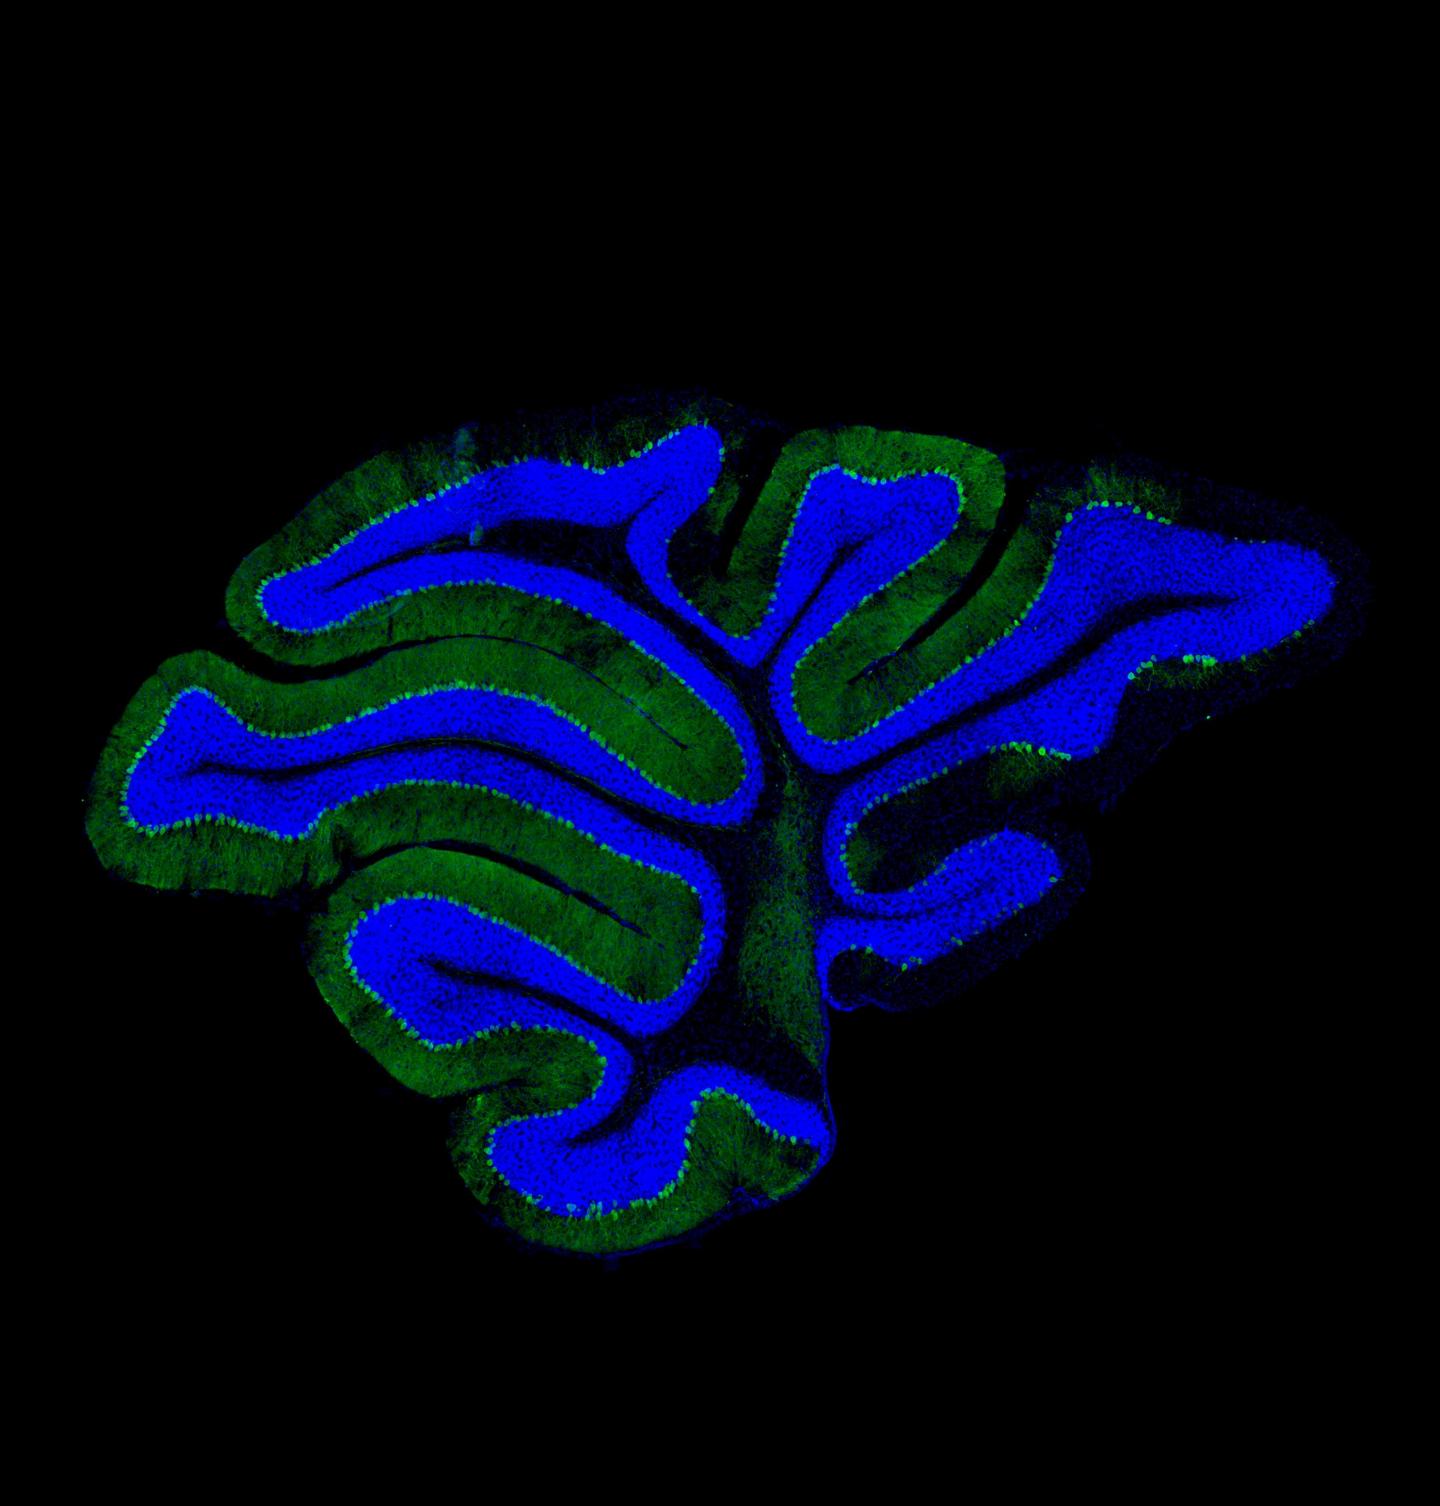

image: Pictured is the cerebellar region of the brain of a mouse lacking the Golgi protein GM130 with the Purkinje neurons labelled in green and DNA in blue. There is loss of Purkinje neurons in the lobes on the right hand side, which results in inability to coordinate muscle movement (ataxia). view more

Credit: The University of Manchester/Martin Lowe

Working with Chinese colleagues, the Manchester researchers examined the role of the Golgi apparatus in neurons, or brain cells, and found that mice in which the apparatus was disabled suffered from developmental delay, severe ataxia, and postnatal death.